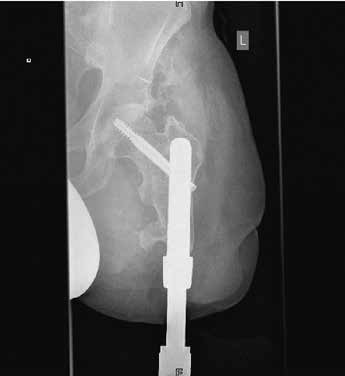

Herr M. S., geb. 1971, hat sich im März 2010 dem ersten Schritt der Operation unterzogen und war davor über 19 Jahre hinweg mit Schaftprothesen versorgt. Dabei erinnert er sich vor allem an die beschwerlich „lange(n) Wege zur Anpassung von Probeschäften bzw. Schäften” und die immer wieder auftretenden Volumenschwankungen des Stumpfes „durch den Abbau der Muskulatur”, was einen korrekten Sitz der Schäfte über längere Zeit vereitelte. Zudem habe er „häufig Haarwurzelentzündungen gehabt”, die durch den Druck der Köcher zustande kamen. Herr M. begrüßt vor allem den durch die Endo-Exo-Prothese „wieder zunehmende(n) Muskelaufbau” des Reststumpfes. Aufgrund einer Läsion des Plexus brachialis mit partieller Lähmung des rechten Arms und der rechten Hand ist Herr M. zwar zusätzlich gehandicapt, jedoch kann er die Endo-Exo-Prothese leicht und selbstständig an- und wieder abbauen, da hierfür nur zwei Schrauben betätigt werden müssen (Abb. 2). Insgesamt sei die Prothese „sehr viel bequemer” für ihn, auch wenn er manchmal Verschleißprobleme mit den äußeren Adaptern gehabt habe. Bei Herrn M. kam es nach einem Sturz zu einer pertrochantären Femurfraktur proximal des Implantates. Er konnte daraufhin mit einem der dynamischen Hüftschraube ähnelnden Osteosynthesemodul versorgt werden, ist seit dem Sturz aber sehr viel vorsichtiger und vermeidet Rotationsbelastungen. Dennoch hat er seit der Versorgung einen Tauchschein gemacht und fährt Fahrrad.

Herr Y. K., geb. 1979, entschied sich für die erste Operation im November 2010 und war davor 3 Jahre unzureichend mit einem Schaft versorgt. Dies lag an seinem sehr kurzen Reststumpf mit obendrein erheblicher Vernarbung. Er habe „alle Schaftsysteme, die es gibt, versucht”, jedoch keine zufriedenstellende Lösung gefunden. Vor allem das Sitzen sei ihm schwergefallen, aber auch „die Hitze im Schaft und wie das riecht” habe er als störend empfunden. Teilweise seien auch die Geräusche bei der Luftentweichung aus dem Schaft „sehr unangenehm” gewesen. Durch das in seinem Fall aufgrund des kurzen Restknochens speziell angefertigte Endo-Exo-Implantat mit proximaler Tragschraube (Abb. 4) habe er nun einen „größeren Bewegungsumfang, und das Sitzen mit der Prothese (auf der Gesäßhälfte der betroffenen Seite, d. Verf.)” sei bequem wieder möglich. Herr Y. arbeitet selbst in der Orthopädie-Technik und bemängelt an der Versorgung, dass teilweise lange Wege unternommen werden müssen, um Ersatzteile der äußeren Bauteile, „die durch Verschleiß ausgetauscht werden müssen”, zu erhalten. Er baut sich selbst äußere Schaumstoffummantelungen für eine bessere Kosmetik, da diese speziell für eine Endo-Exo-Versorgung noch nicht erhältlich seien. Des Weiteren berichtet der Patient, „Bepanthen-Creme (zu) benutzen, um das Stoma weich zu halten” und Hautirritationen zu vermeiden. Seine Körperhygiene beschreibt er als „normal” und ohne größeren Zeitaufwand durchführbar.